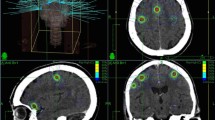

The most common type of brain tumor in adults is brain metastasis, accounting for 10–20% of all cancer patients and surpassing primary brain tumors by tenfold [1]. Lung, breast, melanoma, and kidney cancers account for most primary sites of brain metastases [2]. The symptoms include headaches, neurological deficits, and seizures. 40% of patients report headache as the first symptom, 15-20% have seizures, and 40% have localized neurological deficits such as hemianopsia, aphasia, and hemiparesis. Approximately 65% of patients suffer from cognitive impairment [3, 4].The number of brain metastases appears to have increased during the previous decade, regarding the utilization of magnetic resonance imaging (MRI), enhancement of therapeutic options for systematic disease, aging of the population, and the effectiveness of drugs that do not cross the blood-brain barrier [5,6,7]. The four main definitive therapies are whole-brain radiation therapy (WBRT), surgery, stereotactic radiosurgery (SRS), and medical therapy with chemotherapy, immunotherapy, or precision medicine approaches [8]. Young individuals with limited extracranial disease may benefit from surgical excision of a single brain metastasis, followed by radiosurgery for two to four metastases. The advantages of WBRT after surgery or radiosurgery remain uncertain. Thus, two therapies are available in patients with a favorable prognosis: WBRT after surgery or radiosurgery or observation with MRI follow-up [8].The use of SRS to treat brain metastases in patients has been on the rise. Multiple studies have shown its effectiveness when used alone or combined with WBRT [9,10,11,12]. Radiation therapy with SRS delivers a high dose of radiation to a specific area of an organ while limiting radiation to healthy tissue nearby [13]. An immobilizing head frame is used to immobilize the patient, and stereotactic coordinates target a specific area in the brain and enable precise immobilization and positioning accuracy of less than 1 mm during image capture and treatment [14]. There are several downsides to this intrusive technique, including discomfort and anxiety for the patient. The rigid head frame also requires the presence of a neurosurgeon during installation. Nevertheless, developments in computer engineering, radiologic technology, and radiological methods have offered the potential to transcend the constraints of traditional frames [15].In recent years, non-invasive frameless stereotactic systems have become preferred over traditional patient fixation methods. These frameless systems have shown positional accuracy within the 1–4 mm range, which may vary due to differences in patient fixation, positioning, and accuracy assessment methods [16, 17]. It is crucial to incorporate a small safety margin into the target volume to account for localization and set-up errors, which is essential for minimizing potential treatment-related complications of SRS. Furthermore, the volumes of normal brain tissue exposed to high radiation doses can indicate the development of brain radionecrosis. Studies suggest that brain radionecrosis can occur in up to 47% of treated lesions for brain volumes larger than ten cc receiving a dose of 12 Gy [18].In the current study, we aimed to explore the primary outcomes of frameless SRS, including overall survival (OS), progression-free survival (PFS), local control (LC), and radiological response, and secondary outcomes, including adverse radiation effects, further therapies, and radionecrosis for patients with brain metastases, which can assist neurosurgeons in treating these difficult patients.

SRS characteristics

SRS, with or without WBRT, should be considered as the first-line therapeutic option for BM [55]. Compared to the typical frame-based SRS, non-invasive, frameless SRS improves patient comfort and minimizes anxiety. Frameless SRS also simplifies providing fractionated radiation, which may be effective when BMs are big, irregularly shaped, or located near essential tissues [56,57,58,59,60]. Kondziolka et al. observed a 9% discomfort rate during frame installation despite utilizing sedatives [61]. Furthermore, using SRS without WBRT resulted in fewer adverse effects, such as cognitive impairment [62]. Andrews et al. [9] reported no differences in outcomes between Gamma Knife and LINACs for BMs, whether SRS was used with or without WBRT. The effectiveness of frameless-based SRS for extracranial malignancies has been extensively demonstrated [63].Based on the findings of this meta-analysis, it is evident that frameless radiosurgery leads to improved OS, PFS, and LC rates in patients with BMs. Our study has determined the pooled estimated survival rates at six months, one year, 18 months, and two years for OS and PFS, as well as the six-month and 12-month LC rates. The results demonstrate that a significant proportion of patients experienced improved survival following frameless radiosurgery, with a pooled 6-month OS rate of 75% and a 1-year OS rate of 60%. Moreover, evidence suggests that frameless radiosurgery may offer long-term survival benefits, with estimated OS rates of 48% at 18 months and 39% at two years. Additionally, the PFS rate estimates indicate positive outcomes, with estimated 1-year and 2-year PFS rates of 68% and 75%, respectively, signifying that a substantial number of patients were able to avoid disease progression. Notably, the pooled 6-month and 12-month LC rate estimates showed significant improvement at 93% and 86%, respectively, highlighting the effectiveness of frameless radiosurgery in controlling local tumors.The feasibility and toxicity of CyberKnife Frameless SRS (CK-SRS) were examined in a study. The remaining five patients had a median follow-up length of 19 months. The entire cohort had a median survival duration of 12 months after CK-SRS. The two-year rates for LC, CSS, and OS were 26%, 26%, and 22%, respectively. Symptoms improved or remained stable following CK-SRS, except for one patient who reported greater pain. The treatment was well tolerated, with just one case of Grade 2 and 3 mucositis [64].An analysis of LINAC-based frameless SRS techniques for BM patients was conducted by Ibrahim et al. [65]. Overall, the median survival and time were 8.7 and 5.3 months, respectively. LR as a first event was 25% and 38% after one and two years, respectively, while distant brain recurrence as a first event was 18% and 21%. 31% of patients died before experiencing a brain event. A study examined the outcome and prognostic characteristics of LINAC-based frameless SRS in BM from malignant melanoma. The median follow-up period was seven months, while the median OS was nine months. The 6-, 12-, and 24-month OS rates were 71%, 39%, and 25%, respectively. The median intracerebral control period was 5.3 months, with 6- and 12-month intracerebral PFS rates of 48% and 38%, respectively. The most prevalent clinical adverse effect was headache. The most prevalent radiological result during follow-up was localized edema in the SRS high-dose location [66].Lee et al. [67] studied the effectiveness of VMAT in sequential or simultaneous integrated tumor boost in WBRT for patients with poor prognosis and four or more BMs. The follow-up period spanned 0.3 to 16.5 months. The OS at six and twelve months was 66.7% and 41.7%, respectively. The local PFS at six and twelve months was 100% and 62.5%. In research by Nichol et al. [68], 60 patients with one to 10 BMs who received fractionated therapies were evaluated. At 30.5 months of follow-up, the median survival was 10.1 months, the rates of complete and partial brain response rates were 56%, and LC was 88%. Zhexi et al. [69] investigated the outcomes of frame-based and frameless LINAC SRS. The average follow-up time was 13.2-year s. The total obliteration rate was similar (Frame-based 82.5% vs. Frameless 80.0%) and did not change significantly over time (log-rank p = 0.536). Both frameless and frame-based LINAC SRS are equally successful in obliterating intracranial arteriovenous malformations. In research by Lau et al., single-isocenter frameless VMAT was administered in 15 patients, with a median dosage of 20 Gy in three BMs. The median follow-up period was 7.1 months. At one year, local and regional control was obtained in 81.5% and 60% of cases, respectively, with an OS of 39%; there was no treatment-related toxicity of grade 3 or above. There was no evident link between the dosage administered to normal brain tissue and the level of toxicity [70].An experiment examined LC, brain-distant progression (BDP), toxicity, and OS in BM patients treated with hypofractionated stereotactic radiotherapy (HSRT). In 1.2 years after therapy, the median LC rate was 30 months (96.96%), the median BDP rate was 24 months (12.24%), and the median OS rate was 14 months (69.33%). KPS and managed extracranial disease were linked with a considerable survival advantage [71]. In a study of 98 patients with BMs, Kim et al. discovered that HSRT patients had equal LC and OS rates and a decreased risk of toxicity compared to those treated with SRS. This was even though HSRT was utilized on big lesions in difficult places [72].Buss et al. [73] evaluated the LC of BM treated with single-fraction SRS using frameless or frame-based immobilization. The median follow-up duration for frameless SRS was 10.5 months, while framed SRS took 7 months. Patients treated with frameless SRS had greater neurological symptoms before treatment and were more likely to get a tyrosine kinase inhibitor concurrently or within 4 weeks of treatment. The frameless SRS group exhibited a larger average metastatic volume than the frame-based SRS group, although the difference was insignificant. At one year, LC in BM treated with frameless SRS was 92%, compared to 86% for framed SRS. OS was comparable between groups (p = 0.46).